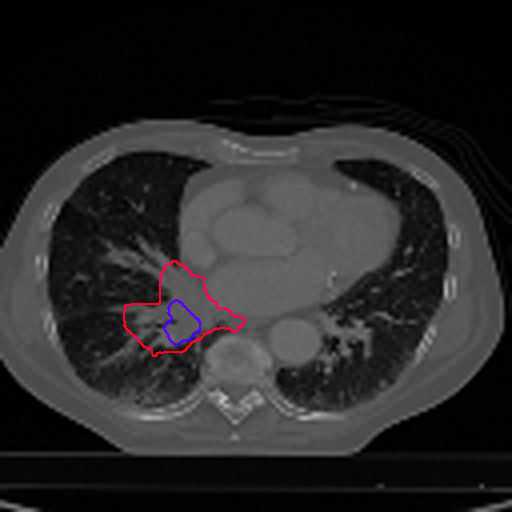

However, in a few rogue cases, where the shapes of the ground truth are exceedingly uncoordinated, perhaps with fissures in the middle or with erratic outlines, it is seen that the predicted tumor regions are prone to imperfections. Although for these cases, our model can predict the existence of tumors, the shapes can often appear to have disfigurements. This is demonstrated in Figure 6. We plan on addressing this issue in our future work.

Moreover, we performed a qualitative analysis on the results produced from the two cases. We observed two things that happen in the absence of wavelet transforms -

-

1.

The predicted tumors seem to have frequent outliers

-

2.

In most cases, the predicted tumor seems to be enlarged and the edges of the tumors are not properly detected

These observations have been demonstrated in Figure 7.

Figure 7 shows the occurrence of outliers in the absence of wavelet transforms and an inability to accurately determine tumor edges in this case. The intuition concerning the former observation is that without wavelet transforms, texture information is relatively lost and the model perceives similarly shaped structures to be tumors as well. The second observation is also related to the fact that wavelet transforms can capture the texture better. In absence of it, the model cannot predict or justifiably limit the extent of the area that the tumor boundary should encompass. This results in inflated tumor areas and inaccurate tumor sizes.